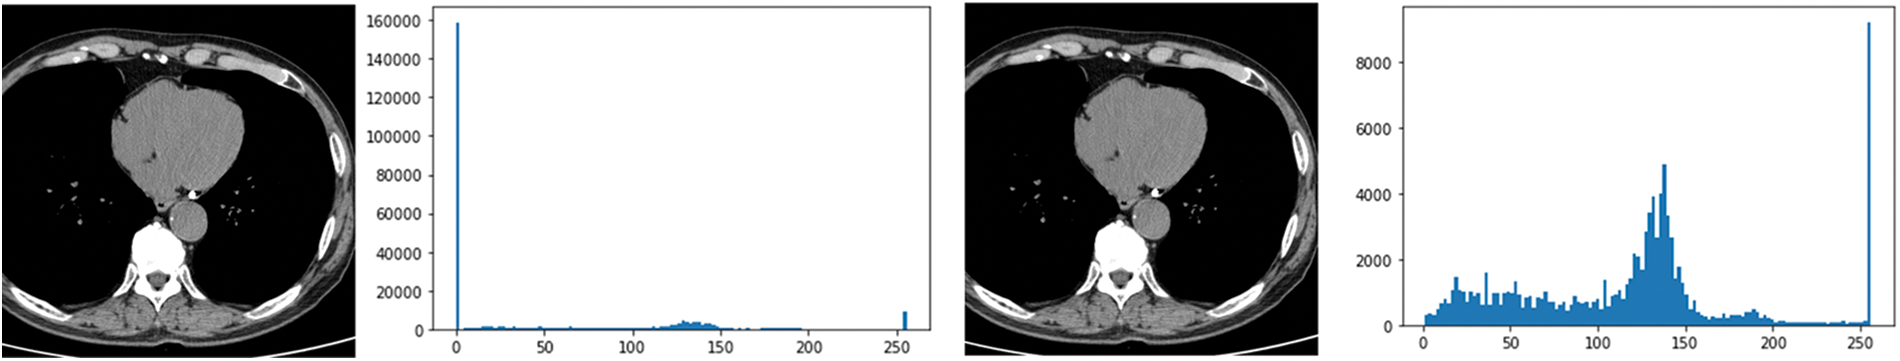

In this paper, the chest CT data has been divided into a ten-image dataset for the original image, K-means Clustering, K-Clustering images with Grabcut, and cropped images from both methods as shown in Fig. 4 were used, and K-means clustering and Grabcut were applied to the original image. In total, 2,400 chest CTs were used, 2,400 images through the original and K-means clustering algorithm and 2,400 data through K-means clustering and Grabcut were used. Ultimately, 7,200 pieces of data were used as a result of reducing the calcium-containing area and the calcium-free area to allocate the same ratio. The images were divided into subdivided images, and all image folders were divided into a group in which calcification had progressed and a group in which calcification had not progressed. The idea of not training parts other than the heart in the preprocessing stage came to mind when we expressed the histogram using Opencv as depicted in Fig. 5. However, at first, there were too many dark areas, so I removed 0 from the range [0:256] and changed it more dynamically. After excluding 0, the data of the normal group and the data that had undergone calcification showed a large difference in values at 256, and when the ROI was set and checked as shown in the figure, the progress of calcification could be seen more clearly, OpenCV supports ROI operation for some functions, but at this time, mask image must be passed as a factor. A mask is a binary image made up of zeros and non-zero. That is, 1 to 255 are treated as the same value. When a mask is applied to an image, all pixels that are 0 in the mask are set to 0 in the output image. It can be implemented using multiplication or AND operation for pixels, but the latter is usually faster. If the ROI is set through this masking operation and only the heart area is drawn as a histogram, it will appear as shown in Fig. 6. The value for 256 was 0 for a normal heart, and the value for 256 increased for data with calcification. So, we thought that if we learned by detecting only the heart region, the accuracy would increase because the feature of other organs was not included. The flowchart is described in Fig. 7.

Figure 5: Histogram results in the range [0:256] and histogram results in the range [1:256]